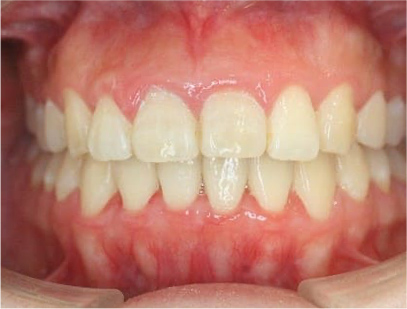

前歯が咬み合っていなく反対咬合の症例

上下の前歯が咬んでない事を主訴として来院されました。通常どおり検査を行い「前歯部に開咬を伴う反対咬合」と診断されました。

上顎は左右4番目の第一小臼歯を抜歯して、また下顎も左右4番目の第一小臼歯を抜歯してその抜歯されたスペースを利用して前歯を上下それぞれ綺麗に並べて咬み合わせを改善する事にしました。また前歯を咬み合わせるためにゴムを使用する事にしました。

上下ともに表側のセラミック(白い矯正装置)

治療前の写真と治療後の写真を比べると口元が治療前は下唇が出ていて、鼻の下が凹んでいました。上顎の前歯のデコボコも綺麗に並びました。また、上下の前歯は開咬が治りしっかりと咬み合ってます。

治療期間は患者様の協力が大変に良かったために2年半とさほど長くはありませんでした。

• 口元が綺麗になった事、上下の前歯が咬み合った事、八重歯が改善された事。